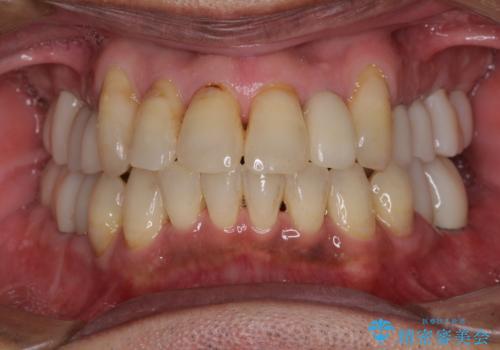

![[MTMを行い歯の神経を保存] 歯周補綴ブリッジの症例 治療後](https://seimitsushinbi.jp/wp/wp-content/uploads/2021/04/75330aaa19199048b71f28658fe46b5b-1-500x350.jpg?v=1618452202)